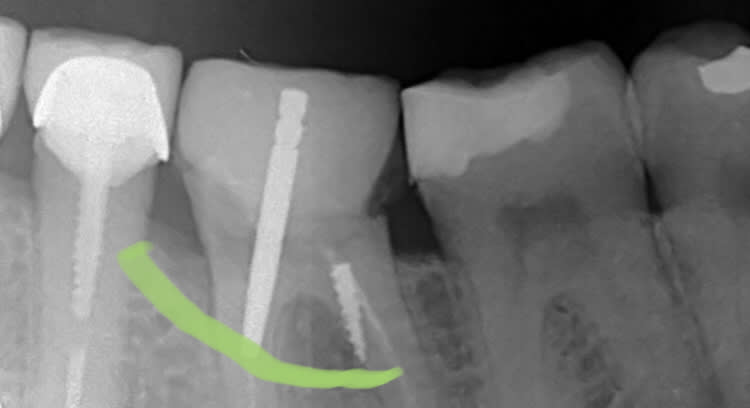

On fait quoi lu1sts - Eugenol

Symptomatique?

asympto, je surveille tous les 6 mois. Un jour faudra peut être faire quelque chose.

La prov est scellée au polycarboxylates, donc étanche.

Je me connais, si elle se descellait, je tenterais une CR avec un moignon compo probablement.

L'implant c'est la facilité...

On sent bien la French touch, en plus c'était pas du low-coast!!

Peut être que le confrère qui a mis le tenon, n'était pas le même que celui qui a posé le screw post ?

Bien vu. Le tenon, c'est pas le souci, tu supprimes le surplomb en Ml, ça redresse l'axe et ... et quoi au fait?-)

Le screw c'est chiant, asympto depuis 15 à 20 ans effectivement.

Perso, je surveille l'espace inter radiculaire et j'attends que ça se descelle... qu'il se passe quelque chose.

je pense reconnaître la même philosophie de soins sur la 45, j'espère pas y toucher:-))

Si ya pas de perfo en regard du screw post je m'en coupe une.

Nan pas fait, c'est asympto et ça changerait rien de faire un 3D (voir les recommandations, la prescription d'un 3D doit apporter un bénéfice, là y a pas)... on le saura le jour le l'autopsie:-)

Personne est pour déposer le screw, bourrer au MTA, rte, IC, CR:-))

Peut etre avertir : "un jour, la ferraille dans la racine risque de perforer votre dent et d'abimer l'os qui, l'entoure , il faudra alors extraire".

Je lui ai fait un bridge il y a 15 ans qui se porte bien... alors tu te doutes qu'elle est zen... on fera la même chose Docteur... sauf que la 5 pas glop!

Tu n’aurais pas une autre radio ? On dirait qu’il y a comme une cuvette ...